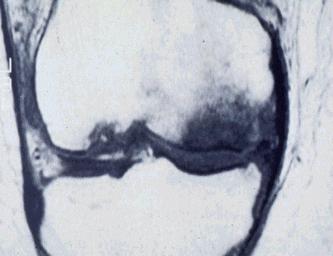

| Osteonecrosi

Una causa relativamente comune di gonalgia nelle persone anziana è l’osteonecrosi.

È più spesso interessato il condilo mediale, ma anche l’esterno ed il piatto tibiale possono essere colpiti.

Le donne sono colpite tre volte più degli uomini, in una fascia di età dai 60 anni in poi.

La maggior frequenza della localizzazione al condilo femorale mediale ha portato a considerare questa lesione come una forma di sofferenza della cartilagine articolare e dell'osso subcondrale e causata da "ipercarico" (eziologia meccanico-traumatica) o da una sofferenza vascolare (eziologia microvascolare).

SINTOMATOLOGIA

Dolore insorto improvvisamente sulla faccia mediale del ginocchio, con gonfiore e limitazione articolare.

Il dolore peggiora alla pressione, di notte e al movimento.

DIAGNOSI

In fase precoce è affidata alla RMN, mentre la radiologia tradizionale mostra le fasi più avanzate del processo. |